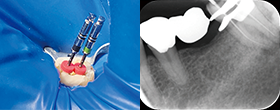

• Edge GlidePath™、EdgeTaper Platinum™、EdgeSequel Sapphire™を使用して二重湾曲根管の形状を残したまま、根管形成を行った例。

エッジグライドパスを使用

Edge GlidePath™

エッジテーパープラチナムを使用

EdgeTaper Platinum™ in MB

XPエンドシェイパーとエッジシークエルサファイアを使用

XP-Endo Shaper(白水貿易)+EdgeSequel Sapphire™ in MB1 & MB2

エッジシークエルサファイアを使用

#35/.04 EdgeSequel Sapphire™